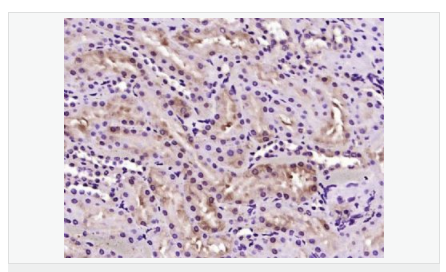

產(chǎn)品介紹LULL1 is a 470 amino acid endoplasmic reticulum single-pass membrane protein belonging to the TOR1AIP family. LULL1 interacts with torsinA, an essential AAA+ ATPase found in the endoplasmic reticulum (ER) and nuclear envelope (NE) of higher eukaryotes. LULL1 regulates the distribution and activity of torsinA within the ER and NE lumen and reveals functional defects in mutant torsinA, which is responsible for DYT1 dystonia, a neurodevelopmental disease caused by an in-frame deletion (Deltagag) in the gene encoding torsinA. The gene encoding LULL1 maps to human chromosome 1, which spans 260 million base pairs, contains over 3,000 genes and comprises nearly 8% of the human genome.